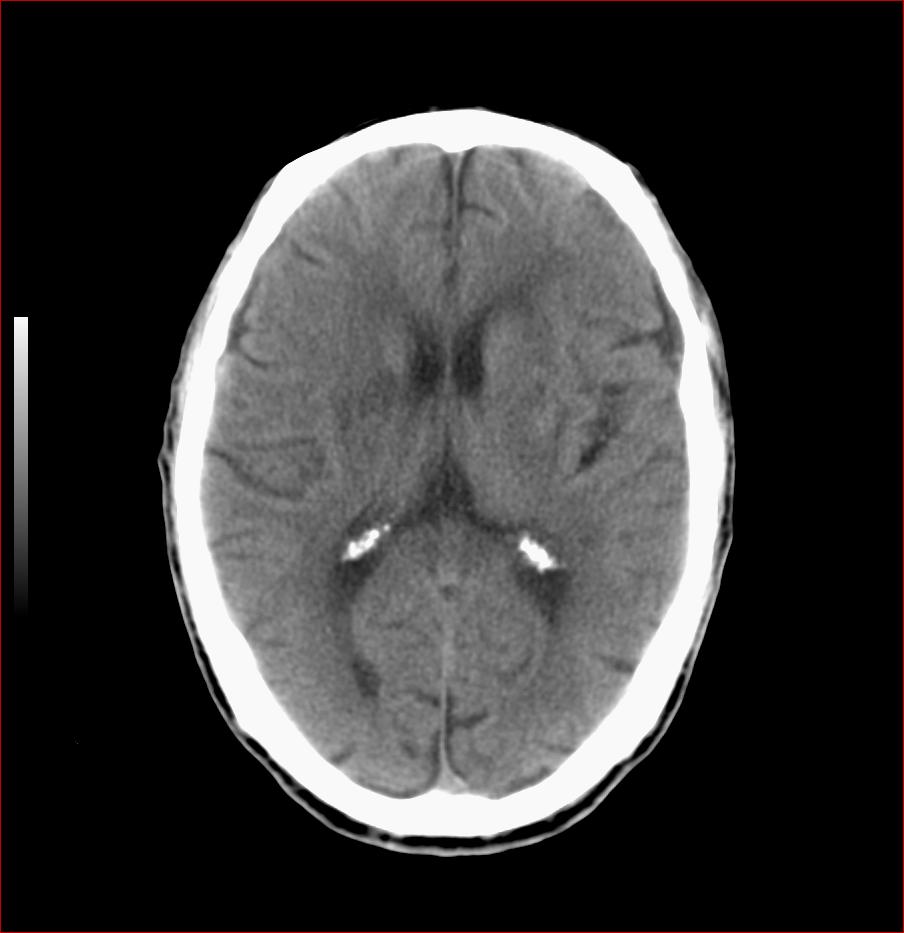

男,84岁,左下肢无力伴口角歪斜1天,血压160/80。请问一下双侧基底节区是脑梗塞吗?

双侧基底节腔梗,脑痿缩

双侧基底节区腔隙性脑梗塞.支持.

多发腔隙性梗死,轻度小脑萎缩。

1.两侧基底节区及右顶深部脑梗塞。2.右侧外囊区脑软化灶。3.脑萎缩。4.脑白质脱髓鞘改变。

1.双基底节区及双顶深部脑梗塞;2.右外囊区软化灶;3.皮层下动脉硬化性脑病.

1 两侧基底节区脑梗塞;

2 右侧壳核区脑软化灶;

3 脑白质脱髓鞘;

4 脑萎缩。